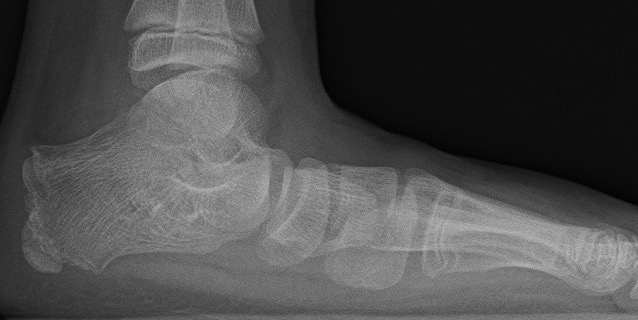

pes planuspes planus

Loss of medial arch on weight bearing

Valgus hindfoot

Flexible flatfoot

Recreation of longitudinal arch & heel varus

- suspended / non weightbearing

- toe raise / windlass mechanism

- passive dorsiflexion of great toe with weight bearing (Jack's test)

Mobile or hypermobile subtalar joint